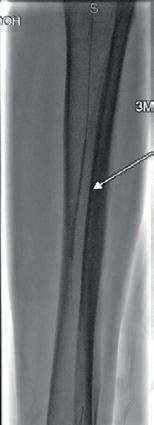

Shockwave E8 3mm x 80mm to the posterior tibial artery

The posterior tibial artery was successfully crossed first. The long-length posterior tibial artery disease was treated with a Shockwave E8 3.0mm x 80mm IVL catheter, with no pre-dilatation required. A total of 200 pulses were delivered along the length of the posterior tibial artery (Figure 3).

Shockwave E8 3mm x 80mm to the peroneal artery

Following this, the peroneal artery occlusion was successfully crossed. The longlength peroneal artery disease was treated with the same Shockwave E8 3mm x 80mm IVL catheter also with no pre-dilatation required. The remaining 200 pulses were

delivered across the length of the peroneal artery disease (Figure 3).